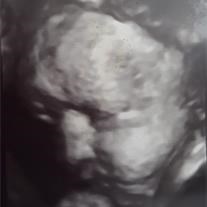

Michelle Natasha Martinez

September 27, 2018 – September 27, 2018

Michelle Natasha Martinez was delivered to Heaven on Thursday, September 27, 2018.